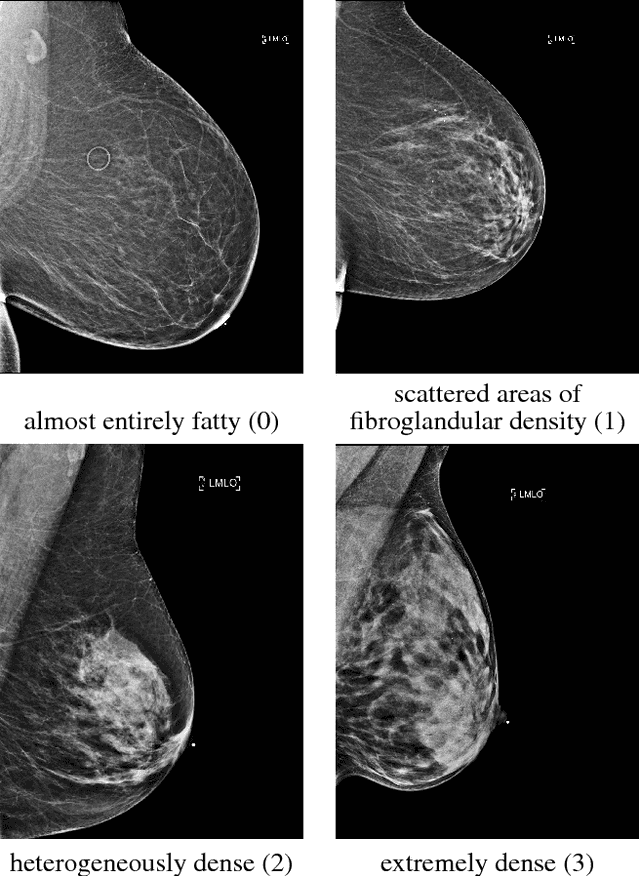

Abstract:Breast density classification is an essential part of breast cancer screening. Although a lot of prior work considered this problem as a task for learning algorithms, to our knowledge, all of them used small and not clinically realistic data both for training and evaluation of their models. In this work, we explore the limits of this task with a data set coming from over 200,000 breast cancer screening exams. We use this data to train and evaluate a strong convolutional neural network classifier. In a reader study, we find that our model can perform this task comparably to a human expert.